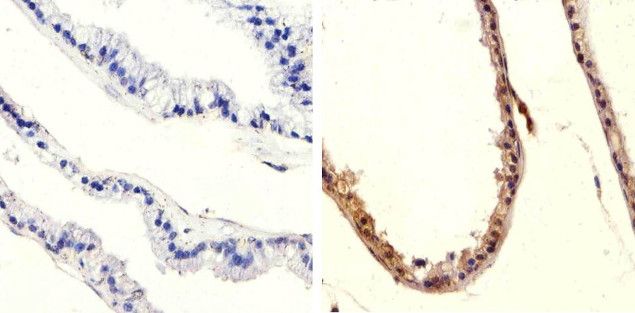

IHC-P analysis of human prostate carcinoma tissue using GTX60929 PTEN (phospho Ser370) antibody.

Right : Primary antibody

Left : Negative control without primary antibody

Antigen retrieval : 10mM sodium citrate (pH 6.0), microwaved for 8-15 min

Dilution : 1:20